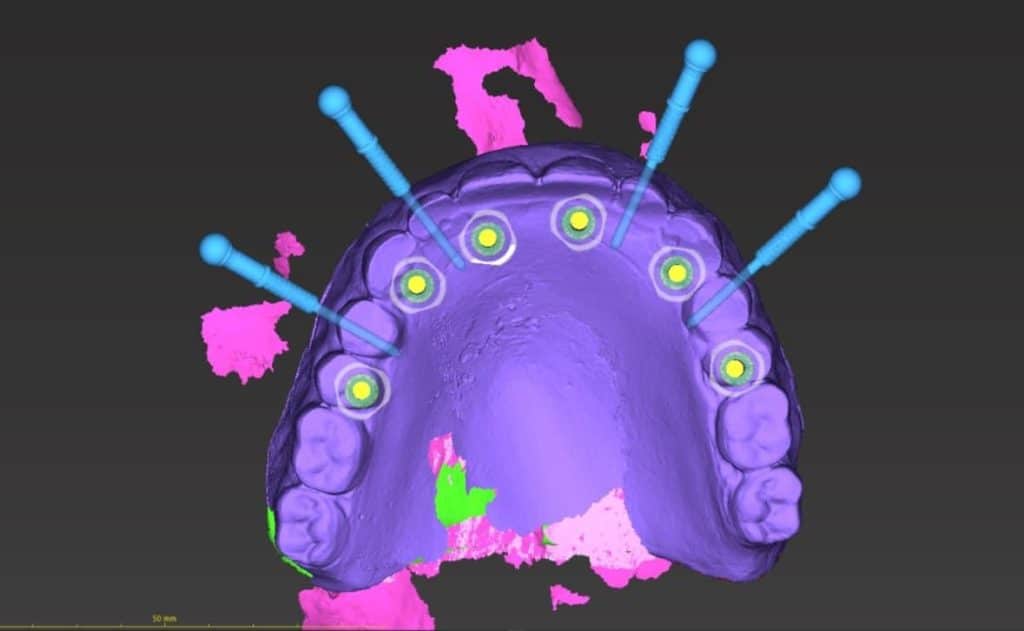

here a case where a full mouth réhabilitation was done by placing 6 implants

multiunit abutement were placed and a temporary bridge also was made for emergence profile shaping